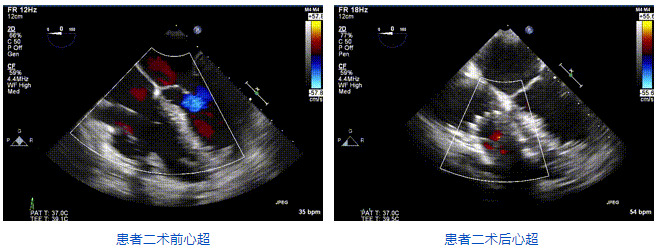

三例患者入院后,葛均波院士團(tuán)隊周達(dá)新教授、潘文志教授、張源博士、陳莎莎博士及心超室的潘翠珍教授、李偉教授對患者的情況進(jìn)行詳細(xì)評估和討論,最終決定為三例患者選擇LuX-Valve Plus40mm、50mm和50mm型號的瓣膜進(jìn)行手術(shù)治療。手術(shù)后即刻拔除氣管插管,術(shù)后患者三尖瓣反流癥狀得到顯著改善,復(fù)查心超結(jié)果顯示人工三尖瓣瓣膜支架固定穩(wěn)定,瓣葉關(guān)閉形態(tài)未見異常,未見明顯反流。